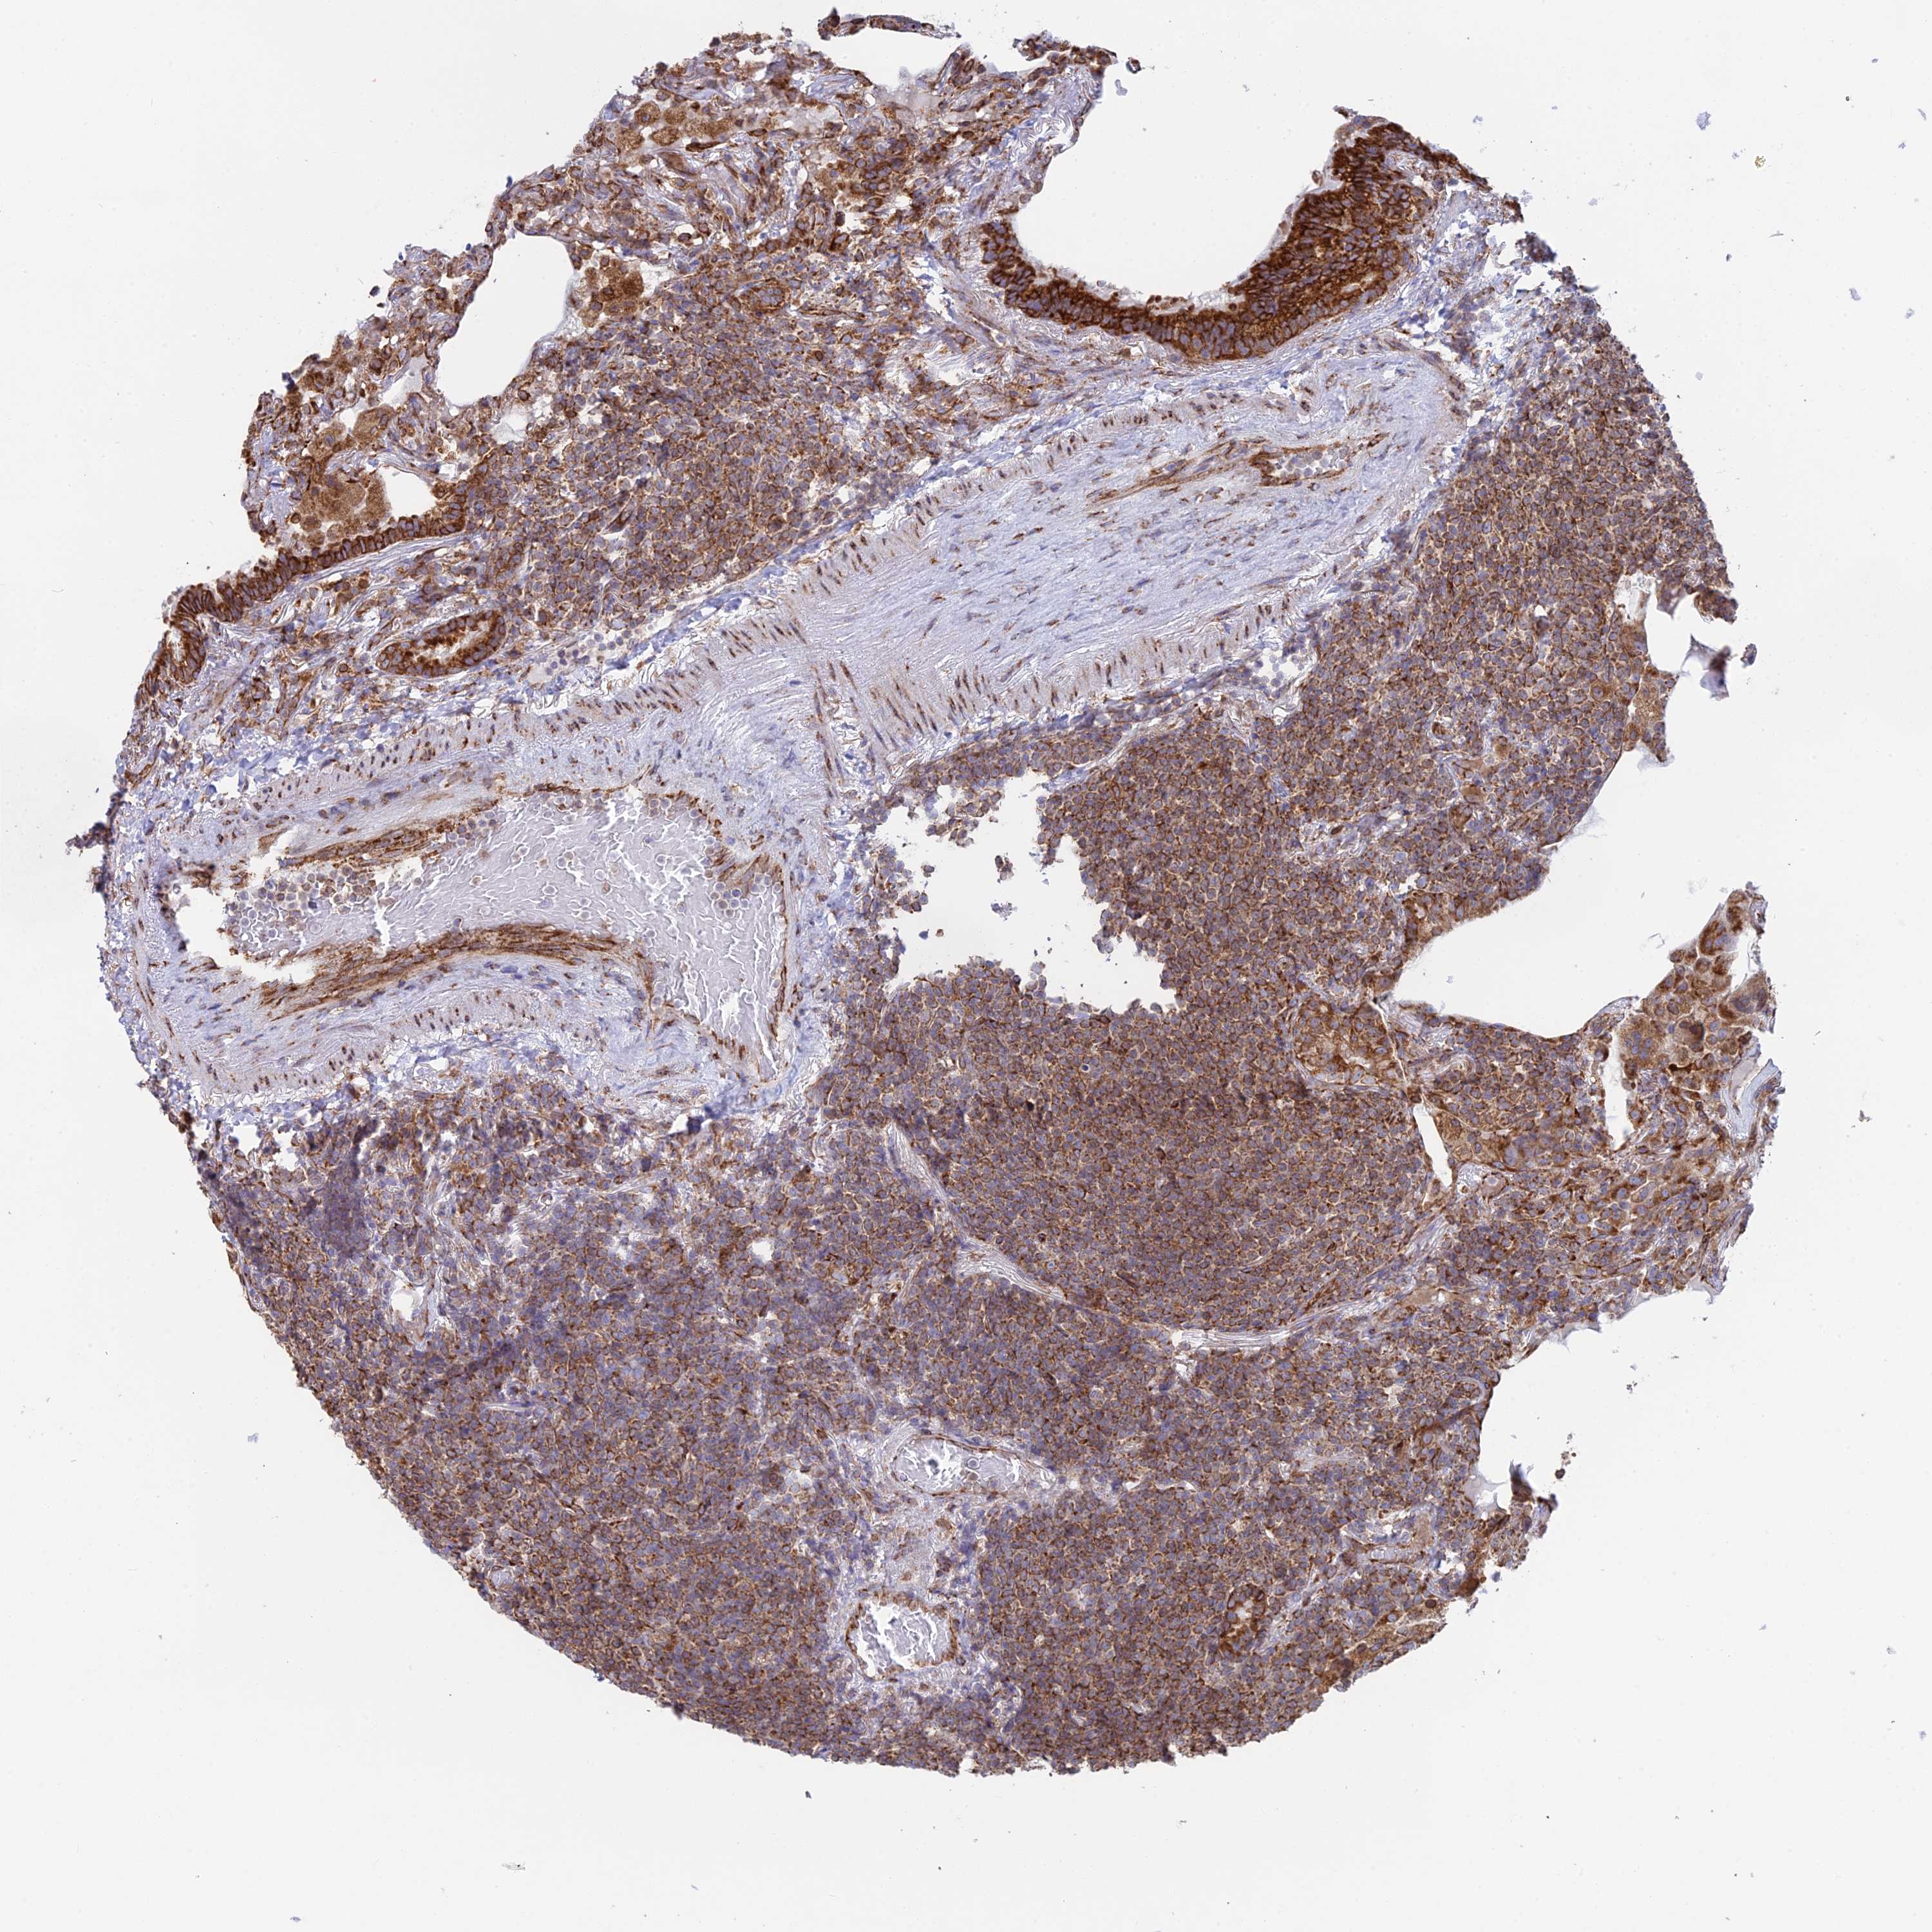

CANCER LYMPHOMA Show tissue menu

LYMPHOMA - Protein expressioni

A mouse-over function shows sample information and annotation data. Click on an image to view it in a full screen mode. Samples can be filtered based on level of antibody staining by selecting one or several of the following categories: high, medium, low and not detected. The assay and annotation is described here.

Antibody stainingi

Antibody staining in the annotated cell types in the current human tissue is reported as not detected, low, medium, or high, based on conventional immunohistochemistry profiling in selected tissues. This score is based on the combination of the staining intensity and fraction of stained cells.

Each image is clickable and will lead to virtual microscopy that enables deeper exploration of all samples and also displays staining intensity scores, fraction scores and subcellular localization as well as patient and tissue information for each sample.

Antibody HPA043648

Staining

High

Intensity

Strong

Quantity

>75%

Location

Nuclear

Hodgkin's disease, NOS

Malignant lymphoma, non-Hodgkin's type, High grade

Malignant lymphoma, non-Hodgkin's type, Low grade